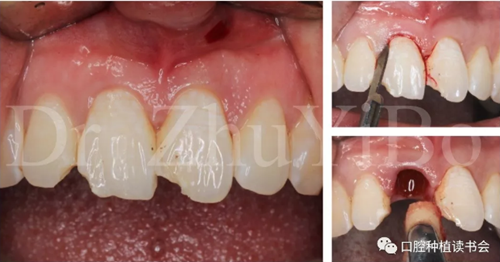

4.2.1微創(chuàng)拔出牙齒,挺出根尖(圖9)

圖9 斷裂牙根需用微創(chuàng)器械拔除

4.2.2 拔牙窩沖洗,定點(diǎn),備洞(圖10)。

圖10 種植窩洞相對(duì)于天然牙長(zhǎng)軸偏向腭側(cè)

4.2.3 植入Nobel active種植系統(tǒng) RP 13mm種植體,植入扭矩大于45Ncm,初期穩(wěn)定性良好(圖11、圖12))。

圖11 使用Nobel active手用植入扳手精確控制植入方向

圖12 種植體初期穩(wěn)定性良好,注意與唇側(cè)骨板間的間隙